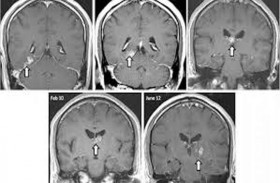

يمكن تجنب الخضوع لجراحة محفوفة بالمخاطر للأشخاص الذين يعانون من كسور الفك الناجمة عن علاج السرطان من خلال مجموعة أدوية متطورة تشفي العظام التالفة. وفي كثير من الحالات يمكن أن يؤدي العلاج الإشعاعي ... إقرأ المزيد